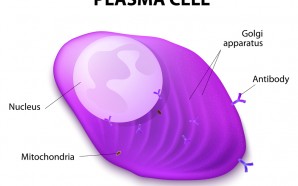

A relapsed myeloma—also known as a recurrent myeloma—is when a cancer mass regrows after treatment. A relapse may also occur while a patient is in remission. Since multiple myeloma does not have a cure, it is likely that, at some point in time, a patient will relapse. When a patient...

Patients with advanced multiple myeloma (MM) whose disease has worsened after multiple lines of therapy have a poor prognosis and very few treatment options available to them. The median survival time for these patients is nine months. The combination of () and low-dose may help some patients if their...